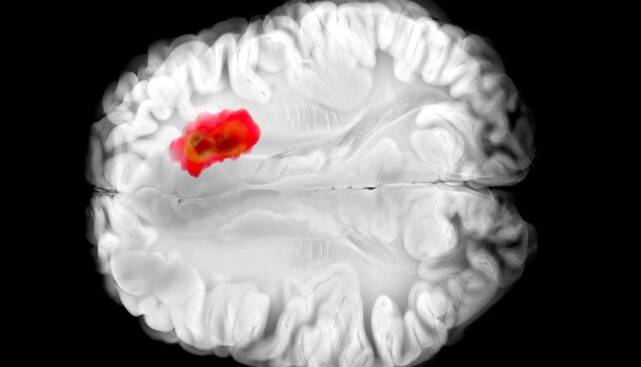

کشف دارویی برای مبارزه با کشنده‌ترین سرطان‌های مغز

تصور می‌شود که همین آنزیم در سرطان‌های مغزی گلیوبلاستومای تهاجمی نقش دارد. این درک جدید از «هیدرالازین» می‌تواند راه را برای درمان‌های جدید سرطان هموار کند و همچنین اثربخشی دارو را برای اهداف فعلی آن بهبود بخشد.

مطالعات قبلی نشان داده‌اند که تومورهای گلیوبلاستوما اغلب سرشار از ADO هستند و آن را برای تولید ماده شیمیایی به نام هیپوتائورین(hypotaurine) می‌ربایند که به سلول‌های سرطانی کمک می‌کند تا گسترش یابند، برای مدت طولانی‌تری زنده بمانند و فشار را تحمل کنند.

در آزمایش‌هایی که با سلول‌های گلیوبلاستومای انسانی انجام شد، «هیدرالازین» با مسدود کردن ADO رشد تومور را متوقف کرد.